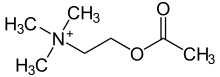

Acetylcholine (ACh) is an organic compound that functions in the brain and body of many types of animals (including humans) as a neurotransmitter.[1] Its name is derived from its chemical structure: it is an ester of acetic acid and choline.[2] Parts in the body that use or are affected by acetylcholine are referred to as cholinergic.

Chemistry

Acetylcholine is a choline molecule that has been acetylated at the oxygen atom. Because of the charged ammonium group, acetylcholine does not penetrate lipid membranes. Because of this, when the molecule is introduced externally, it remains in the extracellular space and at present it is considered that the molecule does not pass through the blood–brain barrier.